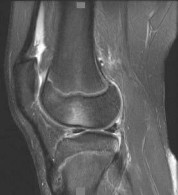

Question 9

A 22-year-old female soccer player sustains a twisting injury to her left knee. An AP radiograph demonstrates a small vertical avulsion fracture of the lateral tibial plateau, distal to the joint line. This fracture is considered pathognomonic for an injury to which of the following structures?

Explanation

The radiograph describes a Segond fracture, which is an avulsion fracture of the anterolateral aspect of the proximal tibia. It is typically associated with avulsion of the anterolateral ligament (ALL) or lateral capsular attachments and is highly predictive (pathognomonic) of an anterior cruciate ligament (ACL) tear.